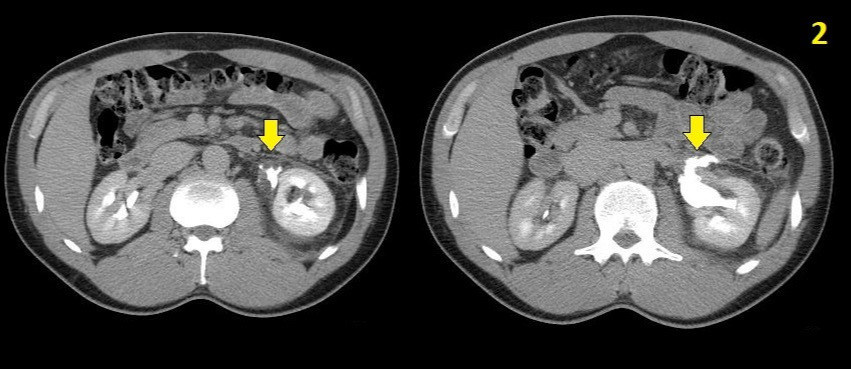

foto2.jpg 노란색 화살표가 가리키는 부위가 요관에서 소변이 새면서 소변종이 발생된 것을 보여줌(화살표가 지목하는 하얀색은 조영제가 섞인 소변)